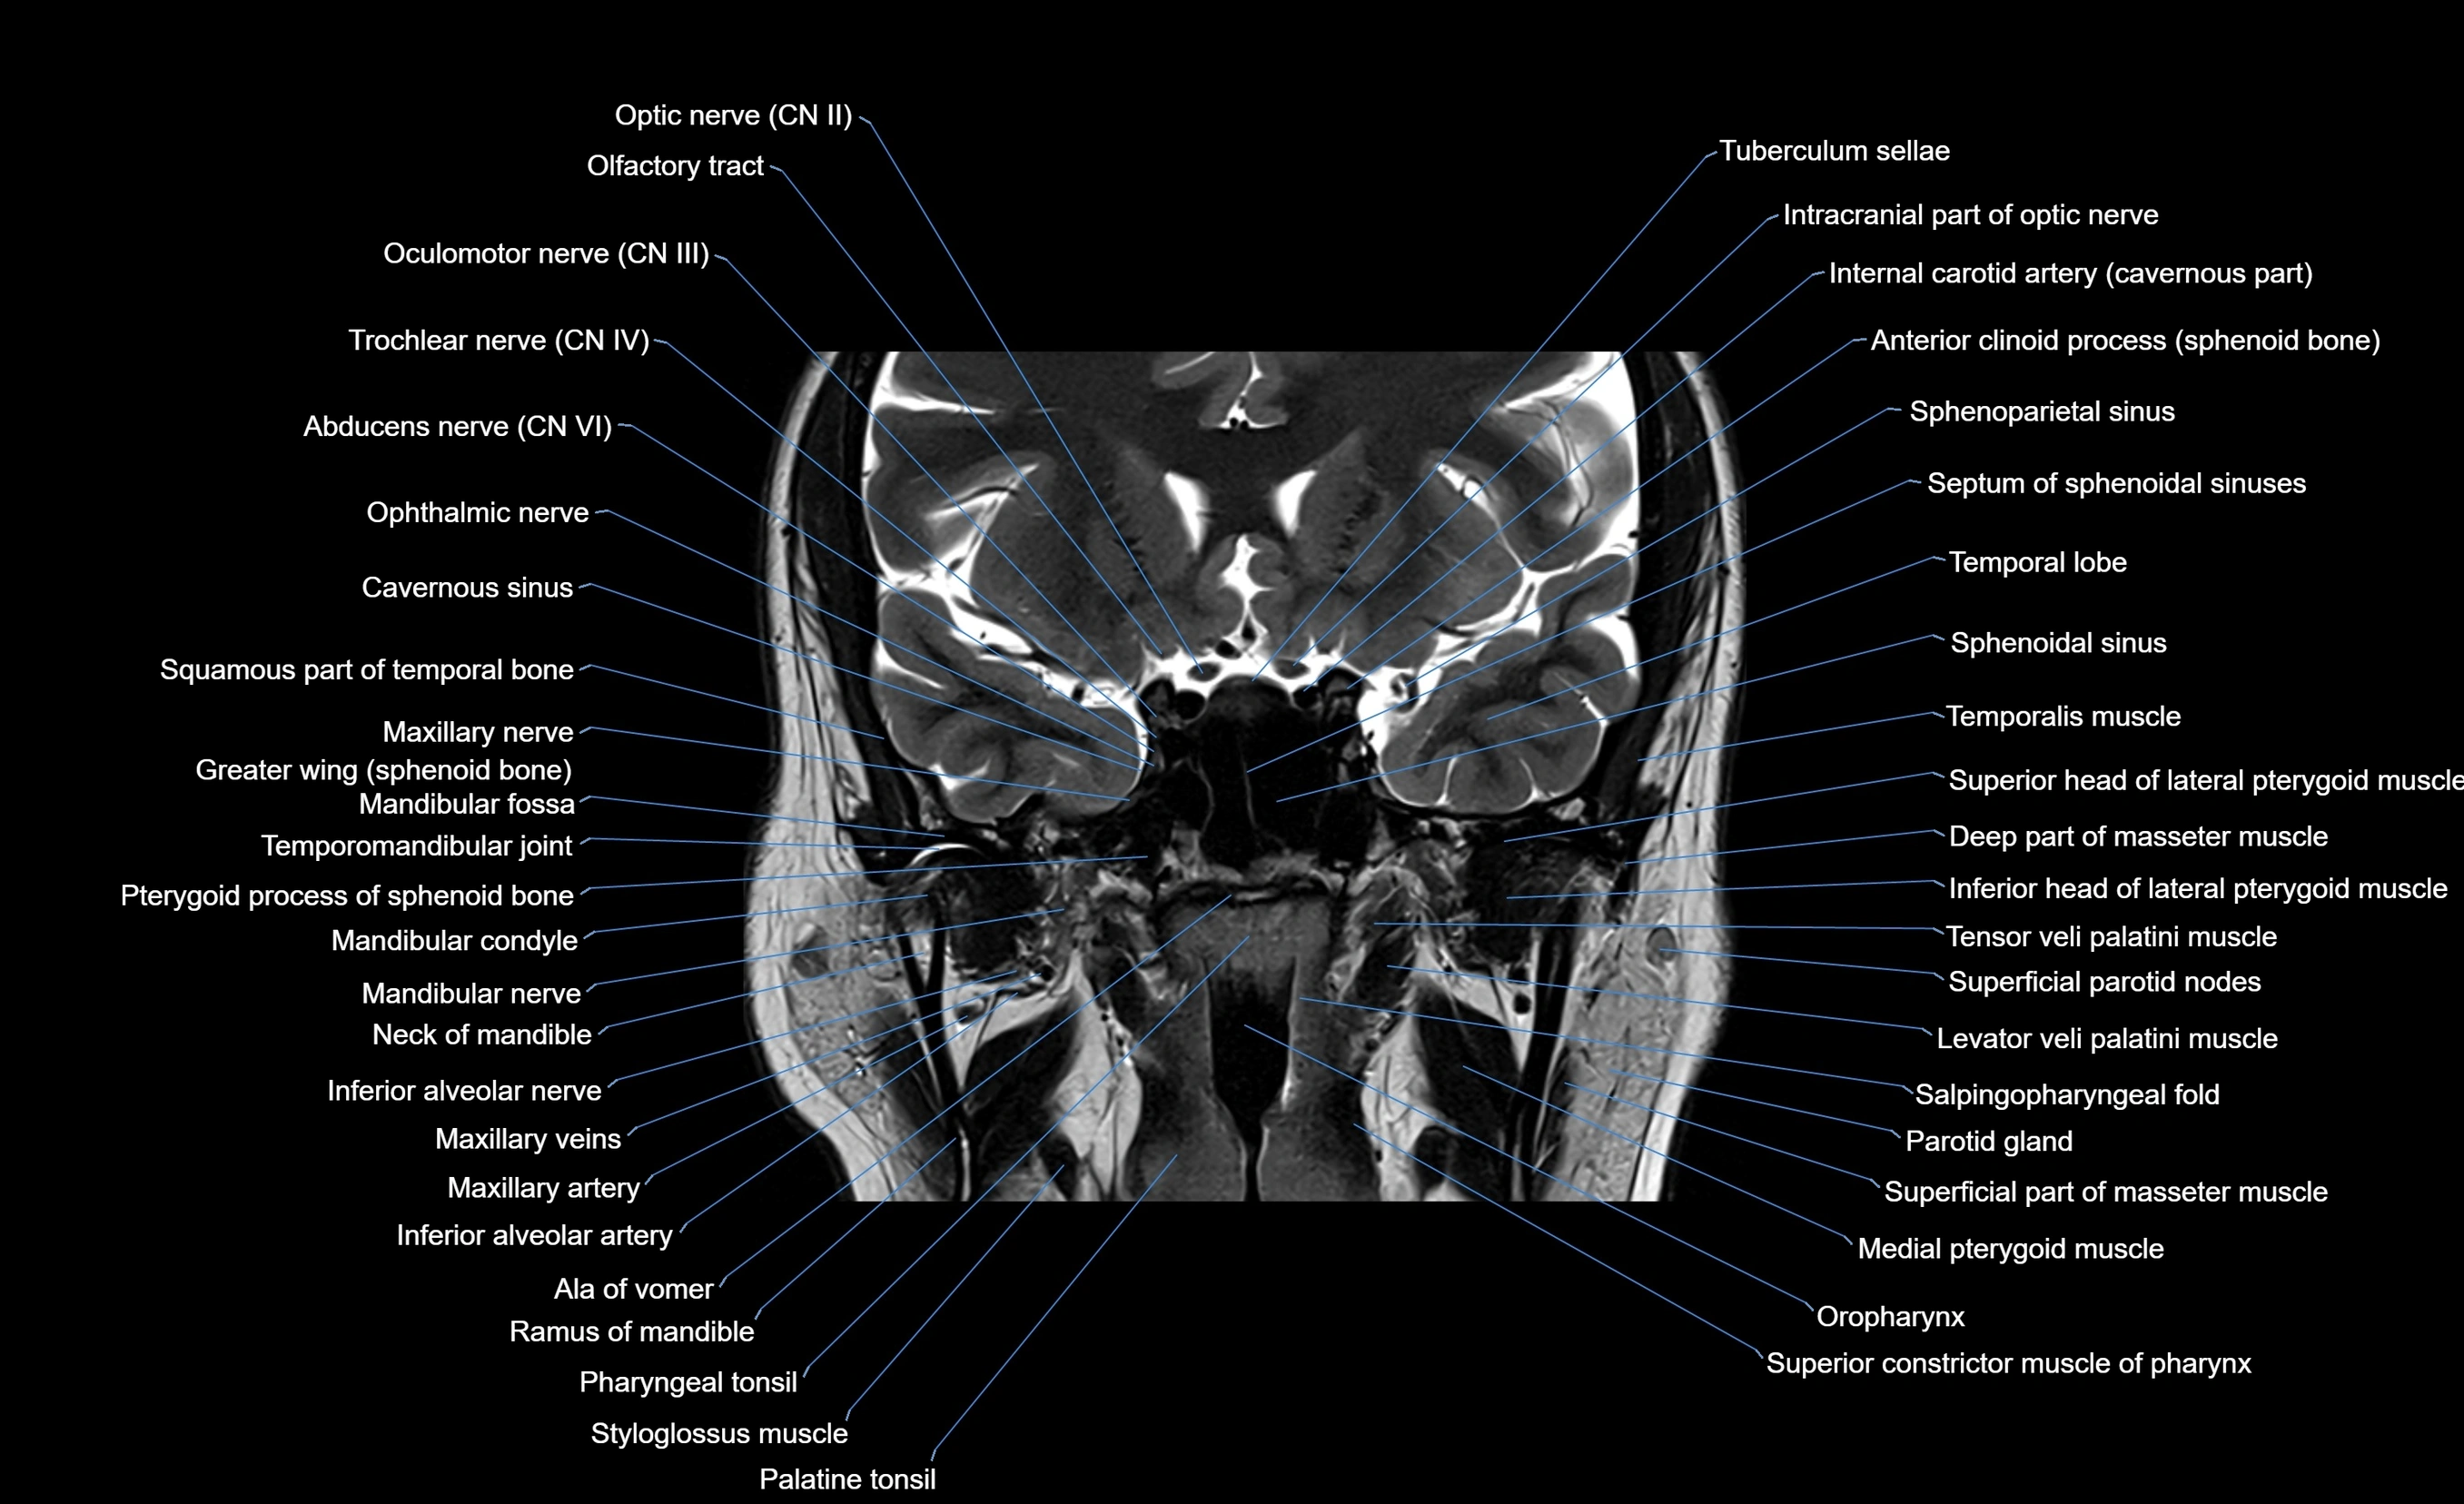

MRI images